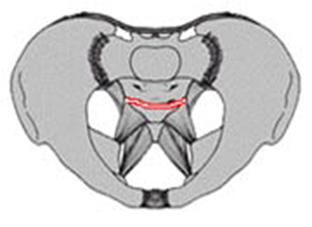

Compresie laterala

Fracturi pelviene multiple Fracturi pelviene multiple

Compresie bilaterala Compresie bilateralaAspect CT

Fracturi pelviene multiple Fracturi bilaterale de ramuri pubiene

Compresie bilaterala Aspect CT Disjunctie sacro-iliaca stanga Compresie antero-posterioara